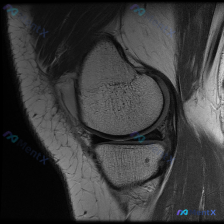

刚看到这个有意思的读片病例,主诉提示半月板异常,但只有单张膝关节MRI T1矢状位图像,整理出来和大家分享思路。 病例核心信息 这次是影像读片场景: 1. 临床提示:怀疑存在半月板异常 2. 影像资料:仅提供单张膝关节MRI T1序列矢状位图像 影像分析所见 先给大家说下这张图的实际表现: - 骨骼...

今天看到一份很有代表性的读片病例,整理出来和大家分享一下,核心问题就是:临床怀疑半月板异常,但是只给了一张膝关节矢状位T1加权MRI,阅片没发现明确异常,这个情况该怎么分析? 先整理一下这份影像资料的基本信息 这是单张膝关节正中矢状位T1加权像,图像质量清晰,没有运动伪影,能看到股骨远端、胫骨近端、...